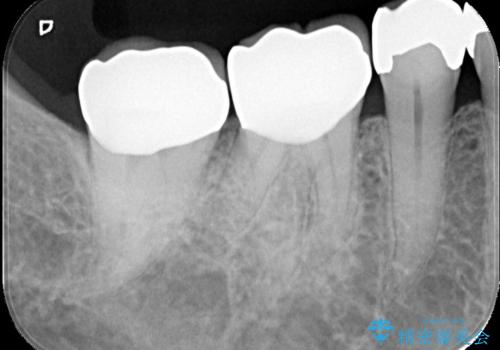

銀歯の下の虫歯|オールセラミッククラウン

- メンテナンスで虫歯が見つかり、治療を行いました。

まず既存の銀歯を除去し、虫歯を取り除いた後、オールセラミッククラウンで修復しました。